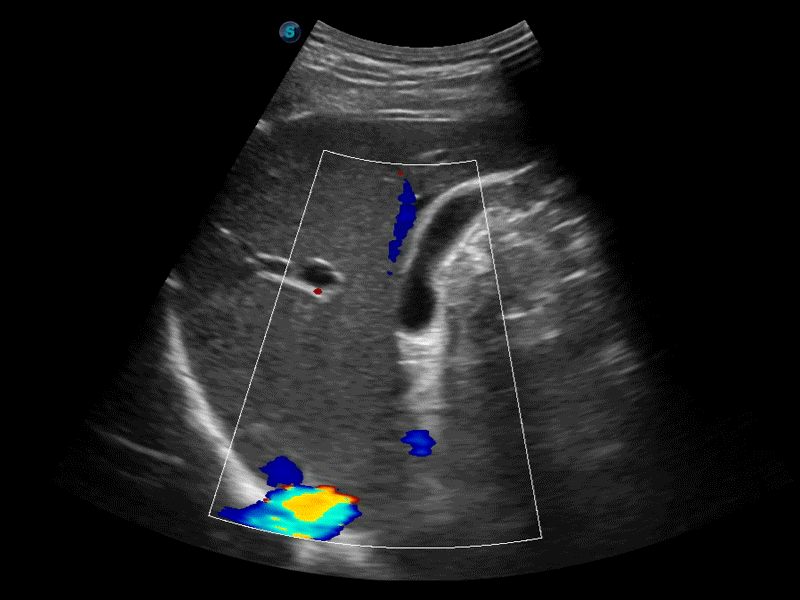

自动识别前后壁内膜厚度,为心血管疾病早期评估提供快速准确依据。

自动识别收缩和舒张末期心肌内膜,自动计算射血分数EF值。